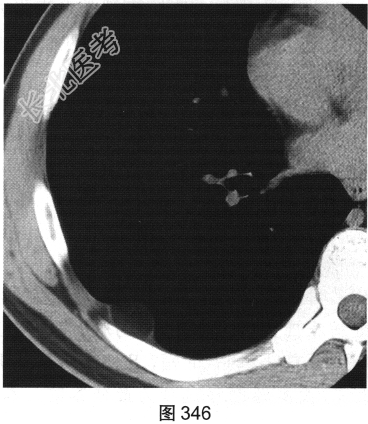

患者男性,43岁,平素健康,偶感深吸气时右后背部不适。近期该患者单位组织体检,在行胸部CT扫描时发现胸壁肿物,见图346、图347。

- 多项选择题1.关于该患者CT图像,正确的描述是( )

A、该肿物呈脂肪密度内伴致密线样影

B、该肿物两侧与胸壁相交呈钝角

C、该肿物可能起源于胸壁软组织

D、右后胸壁可见密度不均软组织肿物

E、右后胸壁可见液性密度包裹性肿物

F、增强后该肿物内部呈轻度不均匀强化